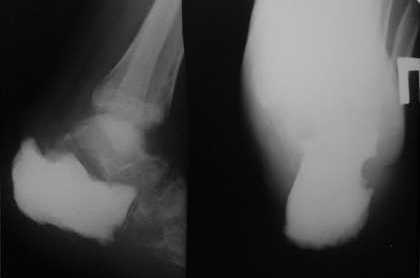

У больного в декабре удалена пяточная кость по поводу хондроcаркомы Б-й Т. 25 лет. Обратился впервые 04.11.09 с новообразованием пяточной кости. Выполнена биопсия, установлен диагноз: высокодифференцированная хондросаркома. ----- произведена экзартикуляция пяточной кости, замещение дефекта цементным спейсером. После операции раны зажили первично. Планировались артродезы голеностопного сустава, таранно-ладьевидного и ауто-аллопластика пяточной кости. В январе онкологами проведён курс лучевой терапии пяточной области и к концу курса, через 1,5 месяца после операции, открылся точечный свищ в середине рубца по медиальной поверхности пяточной области. Отделяемое серозное. Конечность не нагружалась. Госпитализирован в отделение 13.03.10. Взят посев (в работе). Хотелось бы узнать мнения коллег по дальнейшей тактике ведения больного.

Обратите внимание на положение пальцев, отсутствие свода. Даже при отсутствии инфекции на такой ноге ходить невозможно. Вместе с костью ушёл апоневроз, нарушился баланс сухожилий. Вообще спорное решение

было заливать туда цемент.